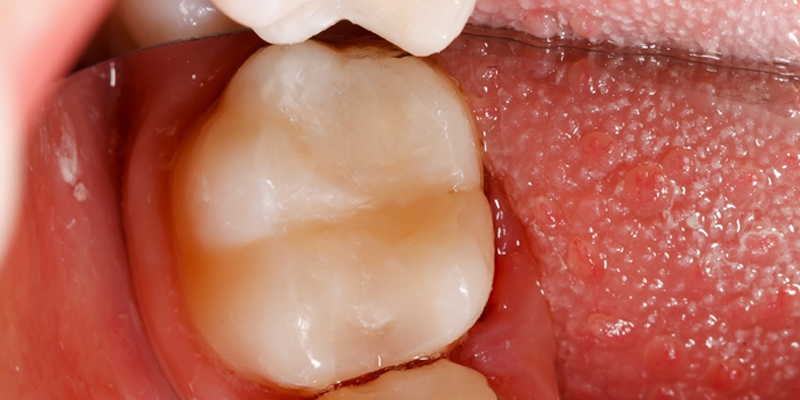

These pictures are a case example of a cosmetic tooth-coloured filling done here at Cornerstone Dental.

Soft decay is removed and the tooth etched.